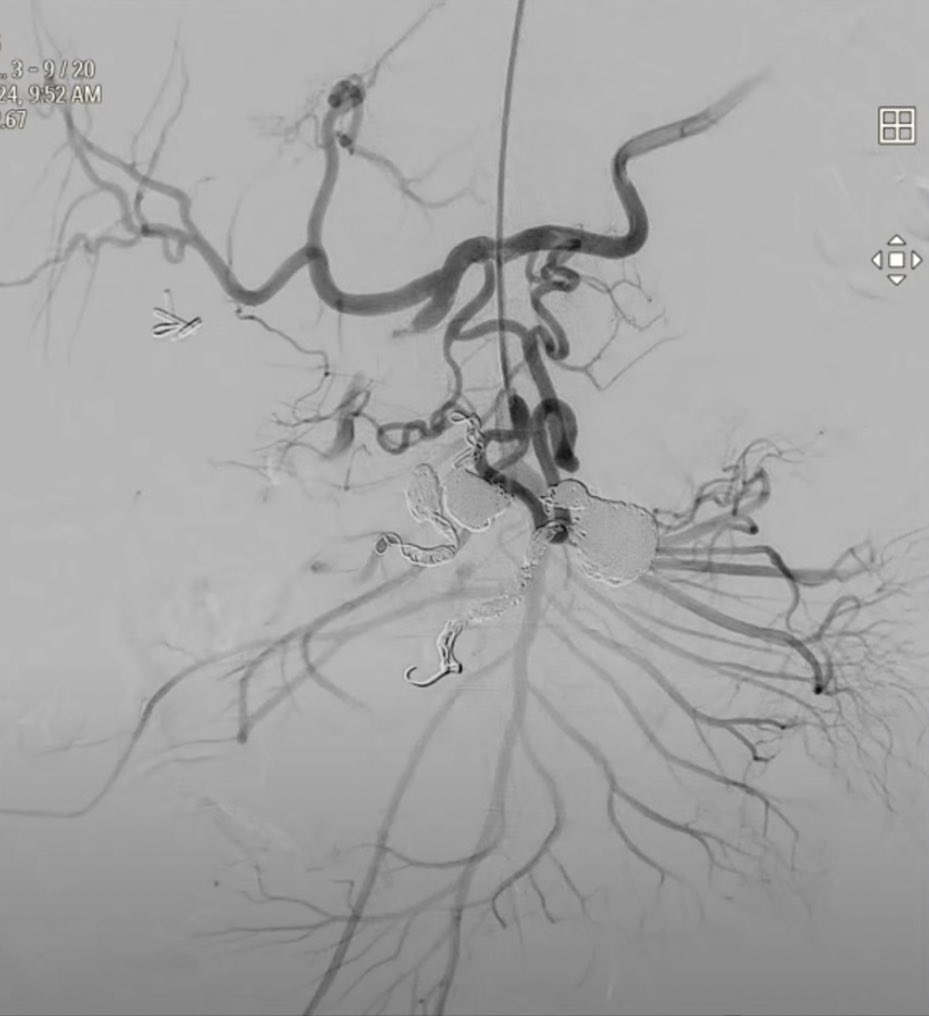

Day 3 #SNIS2023! Check out our project on aspiration thrombectomy in distal vessel occlusion #EVT #stroke • Asymmetric clot engagement w/ Zoom aspiration cath (beveled tip theoretically ⬆️ clot contact surface by 15%) • Safe & highly effective in patients with #DVO stroke

Day 3 #SNIS2023! Check out our project on aspiration thrombectomy in distal vessel occlusion #EVT #stroke

• Asymmetric clot engagement w/ Zoom aspiration cath (beveled tip theoretically ⬆️ clot contact surface by 15%)

• Safe &amp; highly effective in patients with #DVO stroke